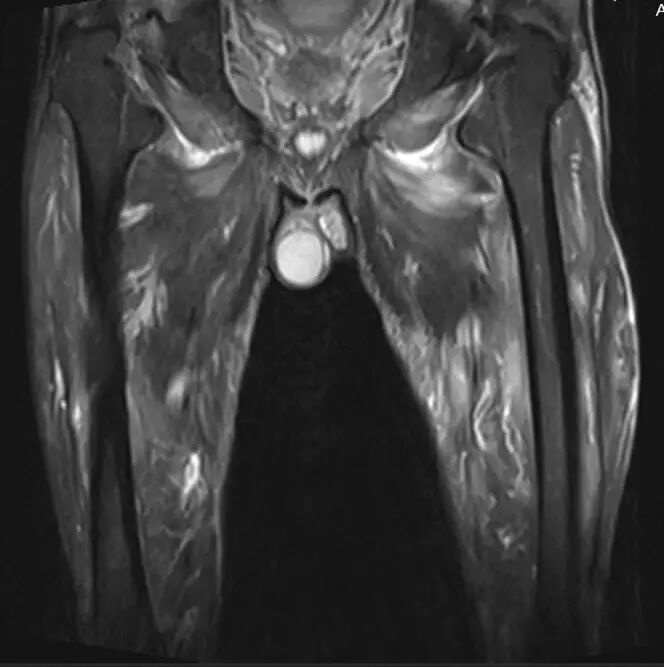

图9.57岁男性特发性肌炎,突然发病的肌肉无力,压痛和无法行走。 冠状短翻转恢复MR图像显示通过骨盆,髋和大腿的大腿肌肉的弥漫性水肿。 肌肉活检揭示“非特异性”肌炎。 症状在6个月的时间内消退,患者能够恢复全身体力活动。

![]()